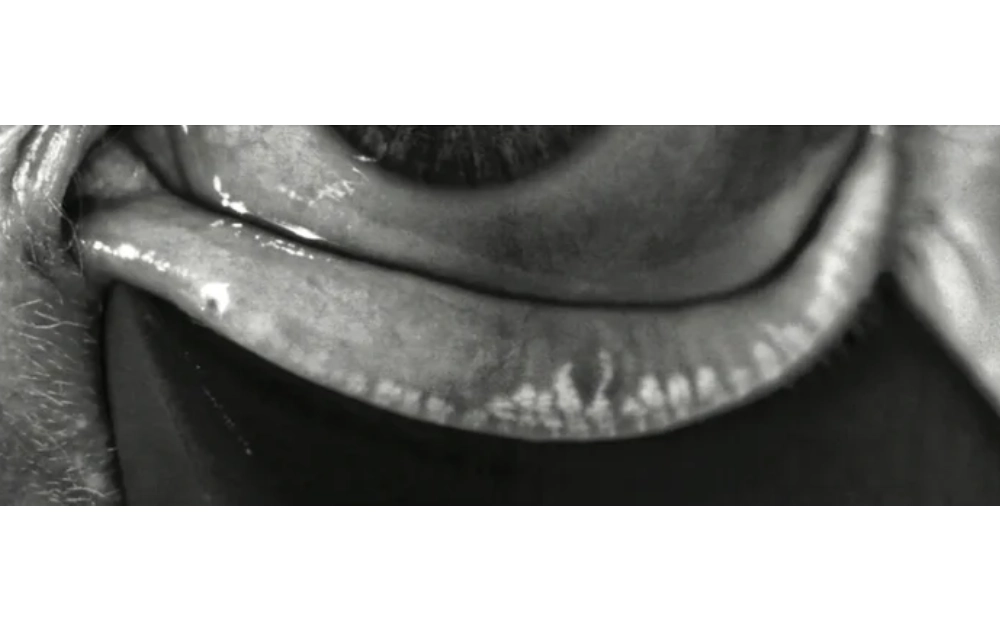

A specialized infrared camera captures images of the inner eyelid to assess gland structure.